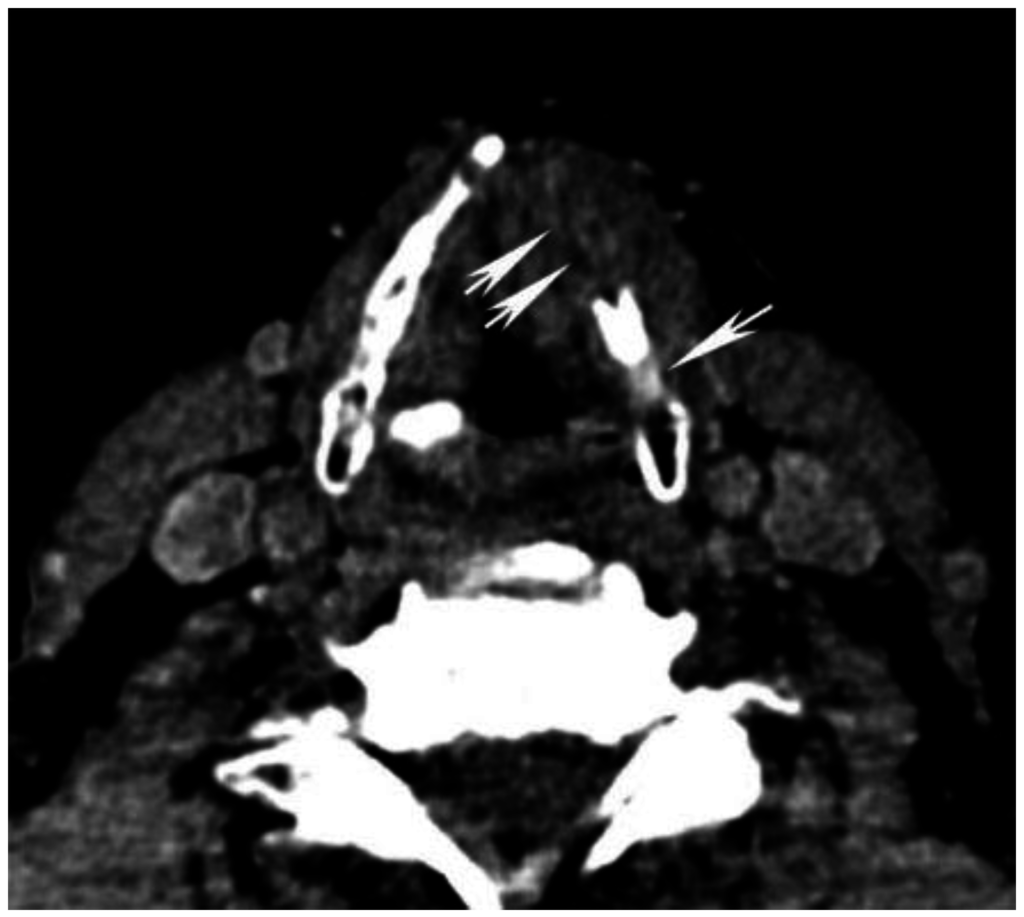

Figure 2. Increased tumor attenuation on 40 keV virtual monochromatic images (VMIs). (A) 70 keV single energy equivalent CT image of a right base of tongue tumor (large black arrow) and pathologic right level IIA lymph node (small white arrow) is shown. Note the similar density of both lesions compared to the normal right sternocleidomastoid muscle (M); (B) On the 40 keV image displayed using the same window-level settings, note the higher lesion density as well as higher relative contrast compared to muscle (M). Also note the increased image noise on the 40 keV VMI (B) compared to 70 keV VMI (A).